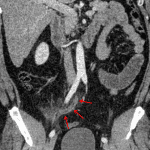

Indication: Right lower quadrant pain

- Distended appendix, measuring 10 mm in diameter with mural thickening and periappendiceal fat stranding

- Acute suppurative appendicitis

Acute suppurative appendicitis without evidence of perforation or abscess.